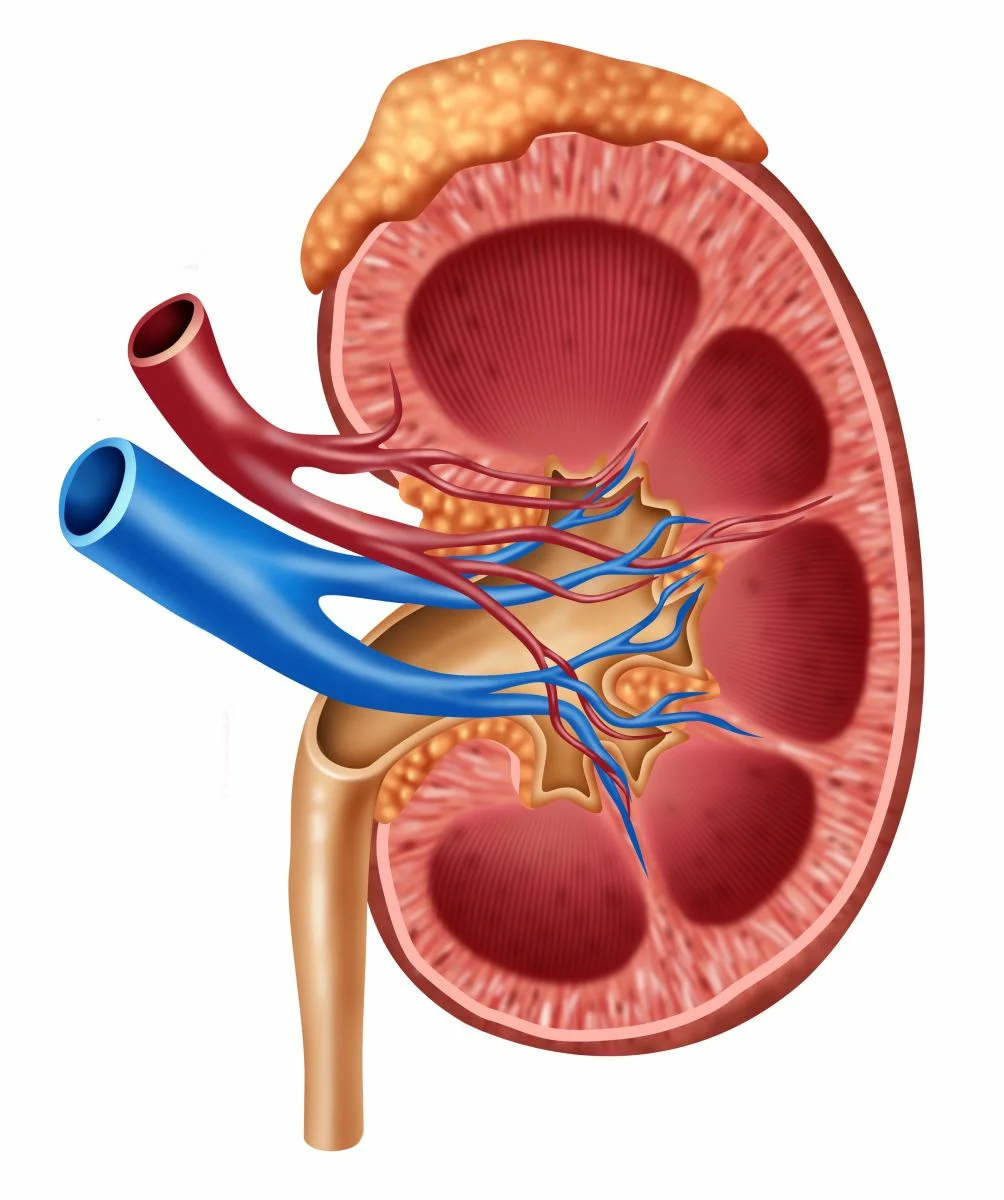

Интраренальная лоханка: рентгеновские снимки и примеры

Раздел: Фотоэссе